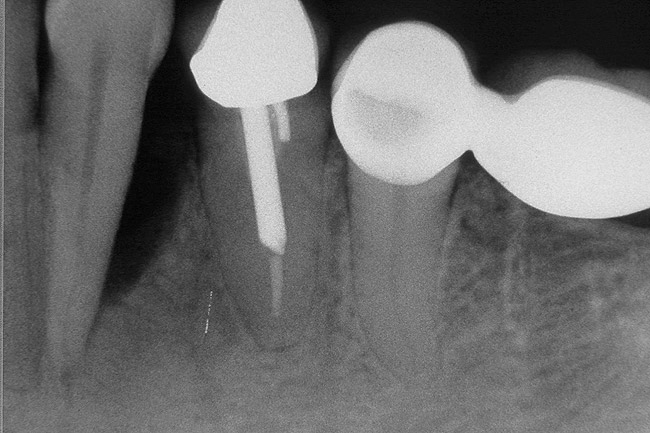

Figure 9  Extraction of teeth Nos. 29 and 31 with immediate implants (Straumann USA, Waltham, MA) placed into the site.

Figure 9

Figure 10  Implants seen in Figure 9 restored approximately 3 months after placement.

Figure 10